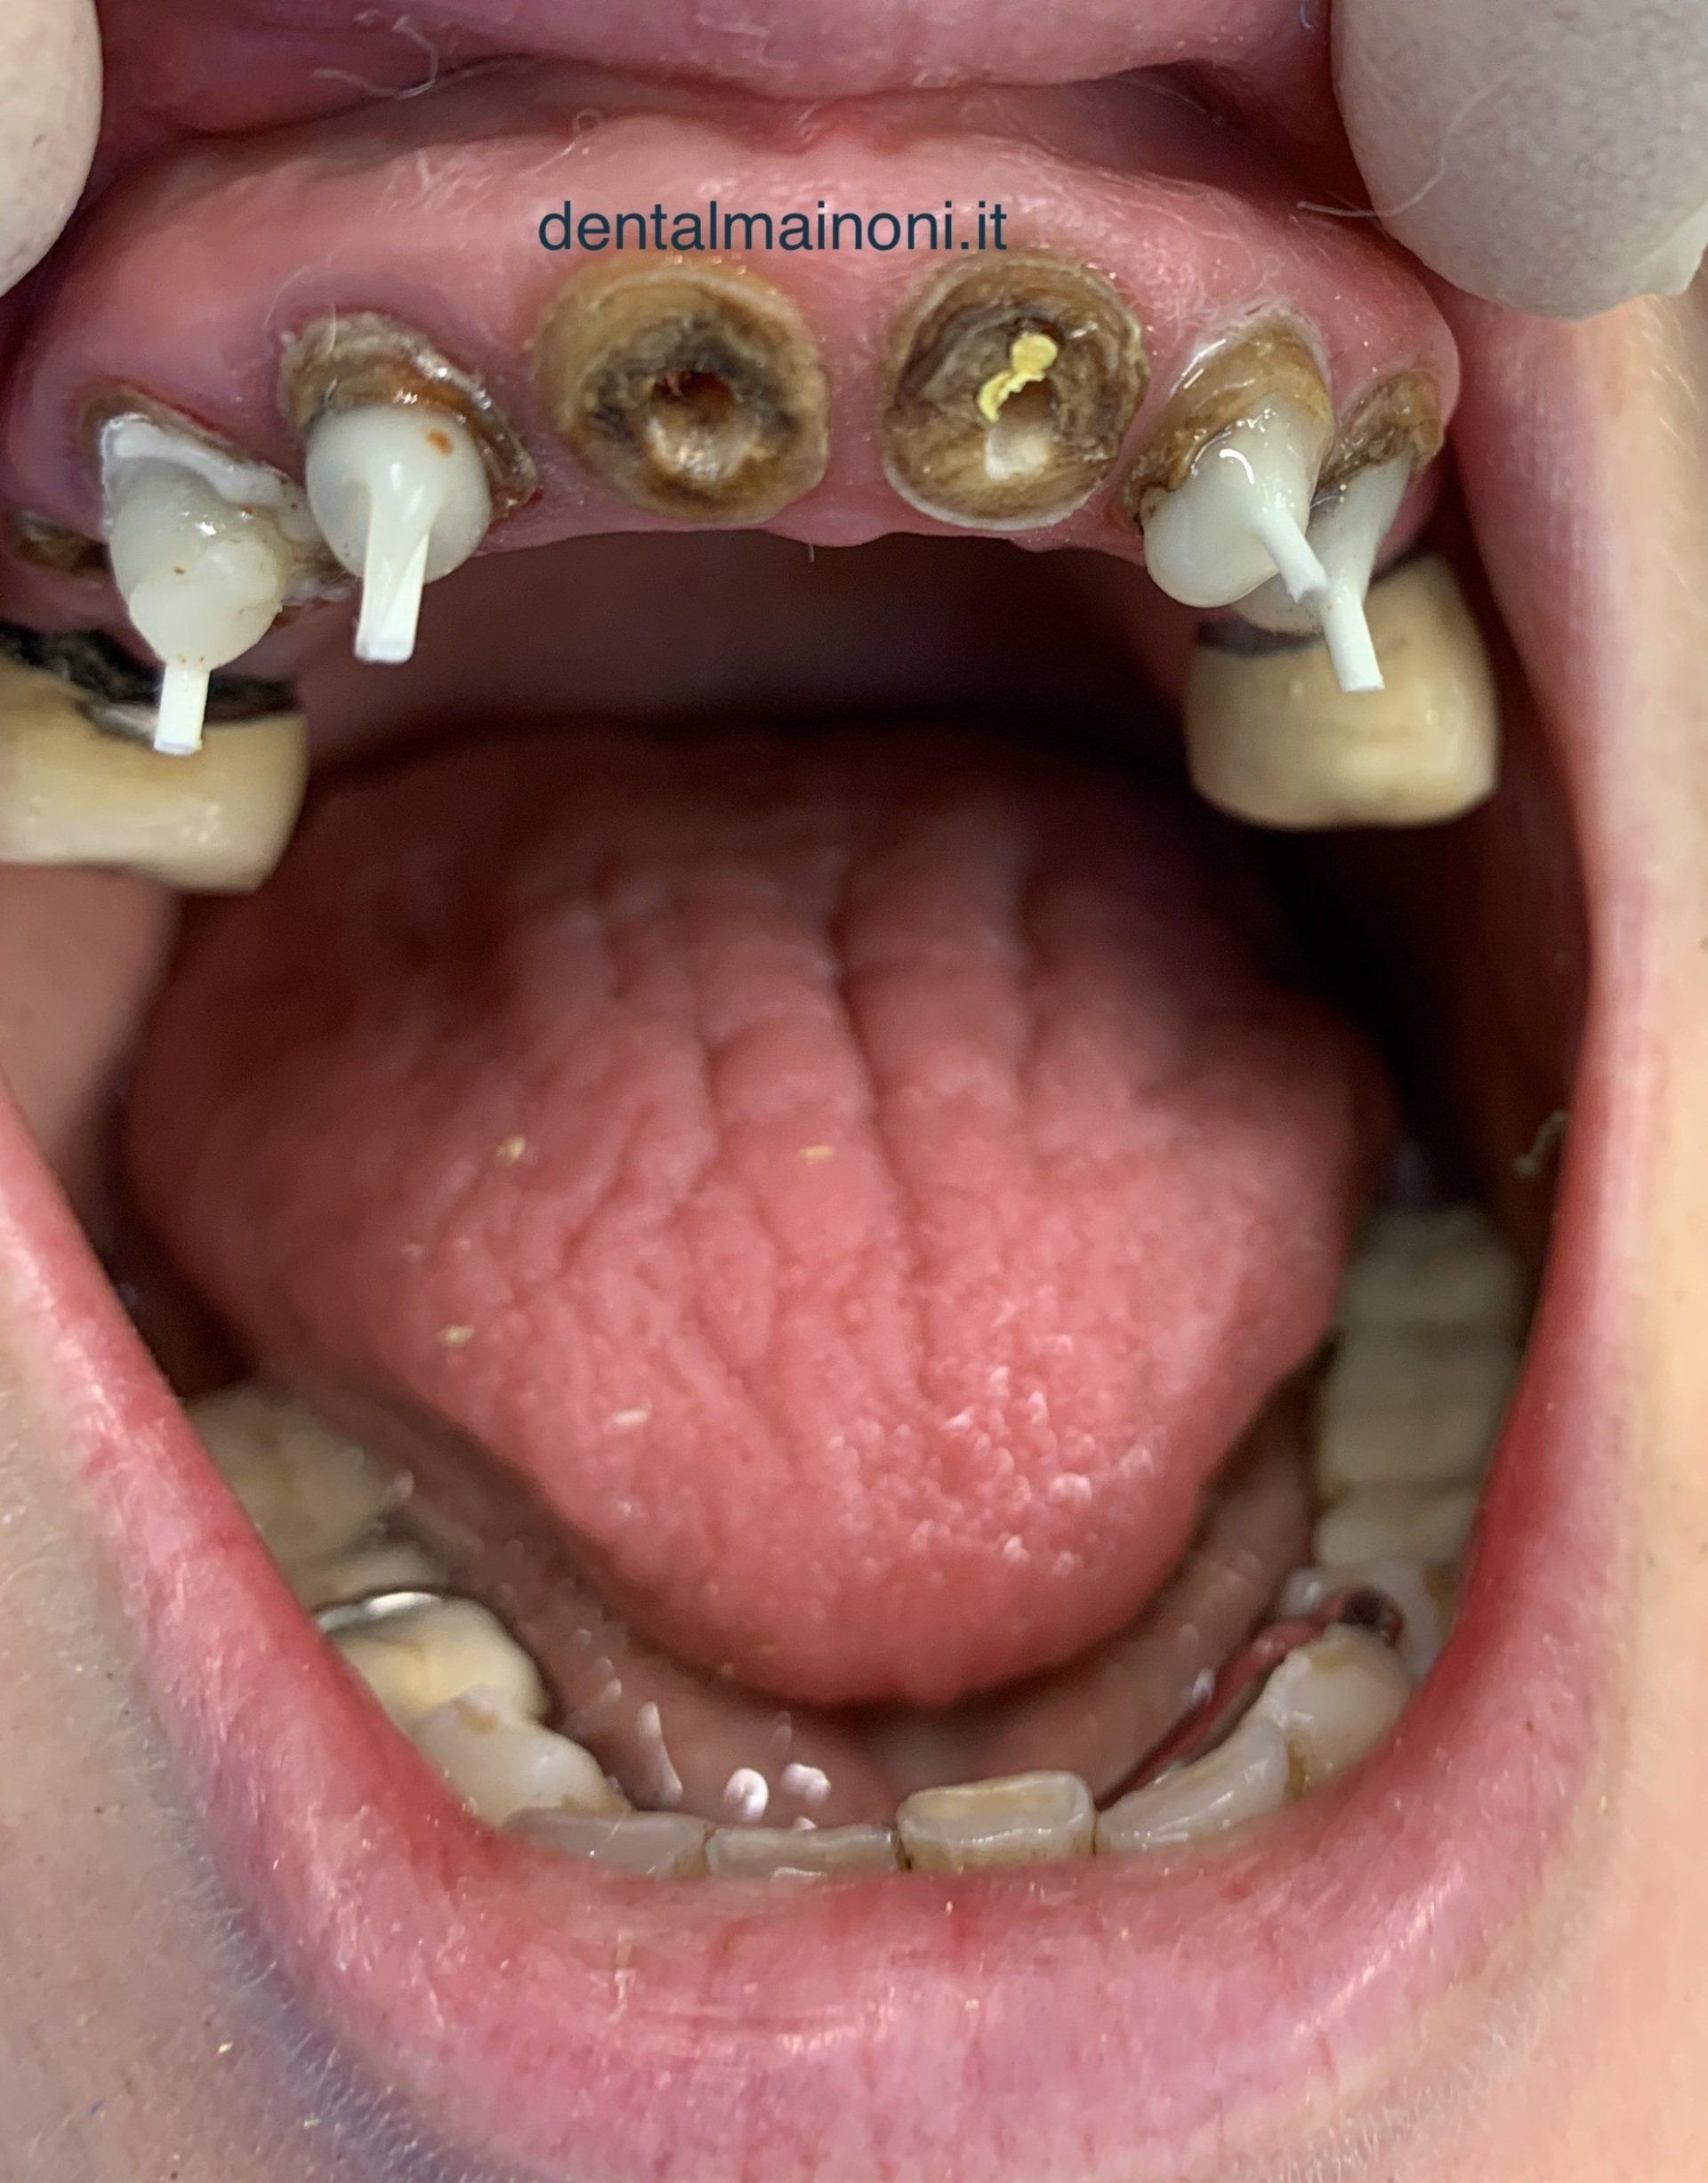

UN'EMERGENZA DENTALE / FOTO 2

ButtonLo scopo principale del trattamento è quello di ricostruire i monconi per poter realizzare immediatamente un ponte fisso, poiché la paziente non accetta una protesi mobile.